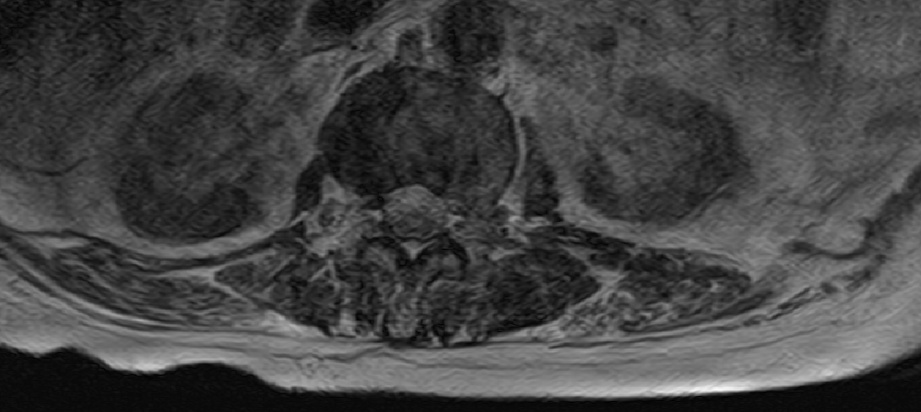

-L Spine MRI

-심한 과호흡 상태에서 검사 시행

-검사 도중 계속 움직임

-Motion Artipact 심하여 scan time 짧게 조정함.

- post L4-5 laminectomy

- flattening of T10 through L2 bodies with partially fatty bone marrow and some sclerotic change

- herniation of discs T10-11 through T12-L1 discs into adjacent vertebral bodies

- L2-3, L3-4 and L5-S1 diffuse bulging discs and ligamentum flavum thickening with indentation of thecal sac and encroachment on neural foramens

- some CSF effacement of L2-3 and L3-4 thecal sac

- partial to circumferential perineural fat effacement of left L5-S1 neural foramen

- decreased T2 signal intensity of discs with osteophytes

1. old T10 through L2 compression fracture with schmorl's nodes

2. L2-3, L3-4 and L5-S1 diffuse bulging discs

3. mild L2-3 and L3-4 central stenosis

4. moderate stenosis of left L5-S1 neural foramen

5. degenerative spondylosis